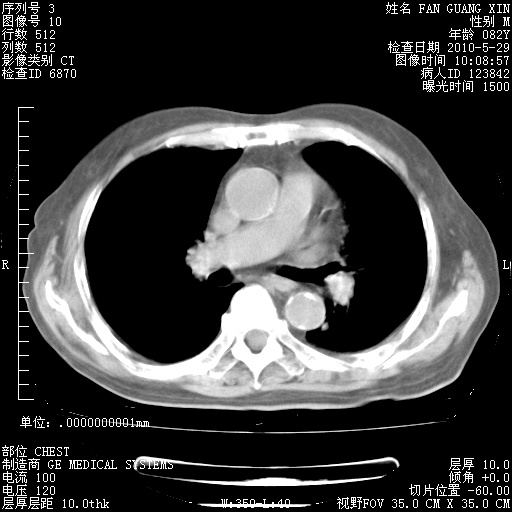

治疗3周后的肺部CT纵隔窗

再治疗10天后的肺部CT 纵膈窗

阅读此次胸部CT,肺间质渗出性改变较入院时有吸收。目前从体温、白细胞、中性分叶明显增高,肯定存在细菌感染(发生医院感染哦,若无消化道及泌尿系统等感染的依据,肺部感染可能大)。若你院头孢哌酮舒巴坦钠耐药率较高,同意你的方案,若48小时体温仍高,可考虑使用碳青霉稀类抗菌药物,同时可予超声雾化、注意滴数时加大液体量。白蛋白33.30g/L较低哦,需加强营养等支持治疗。